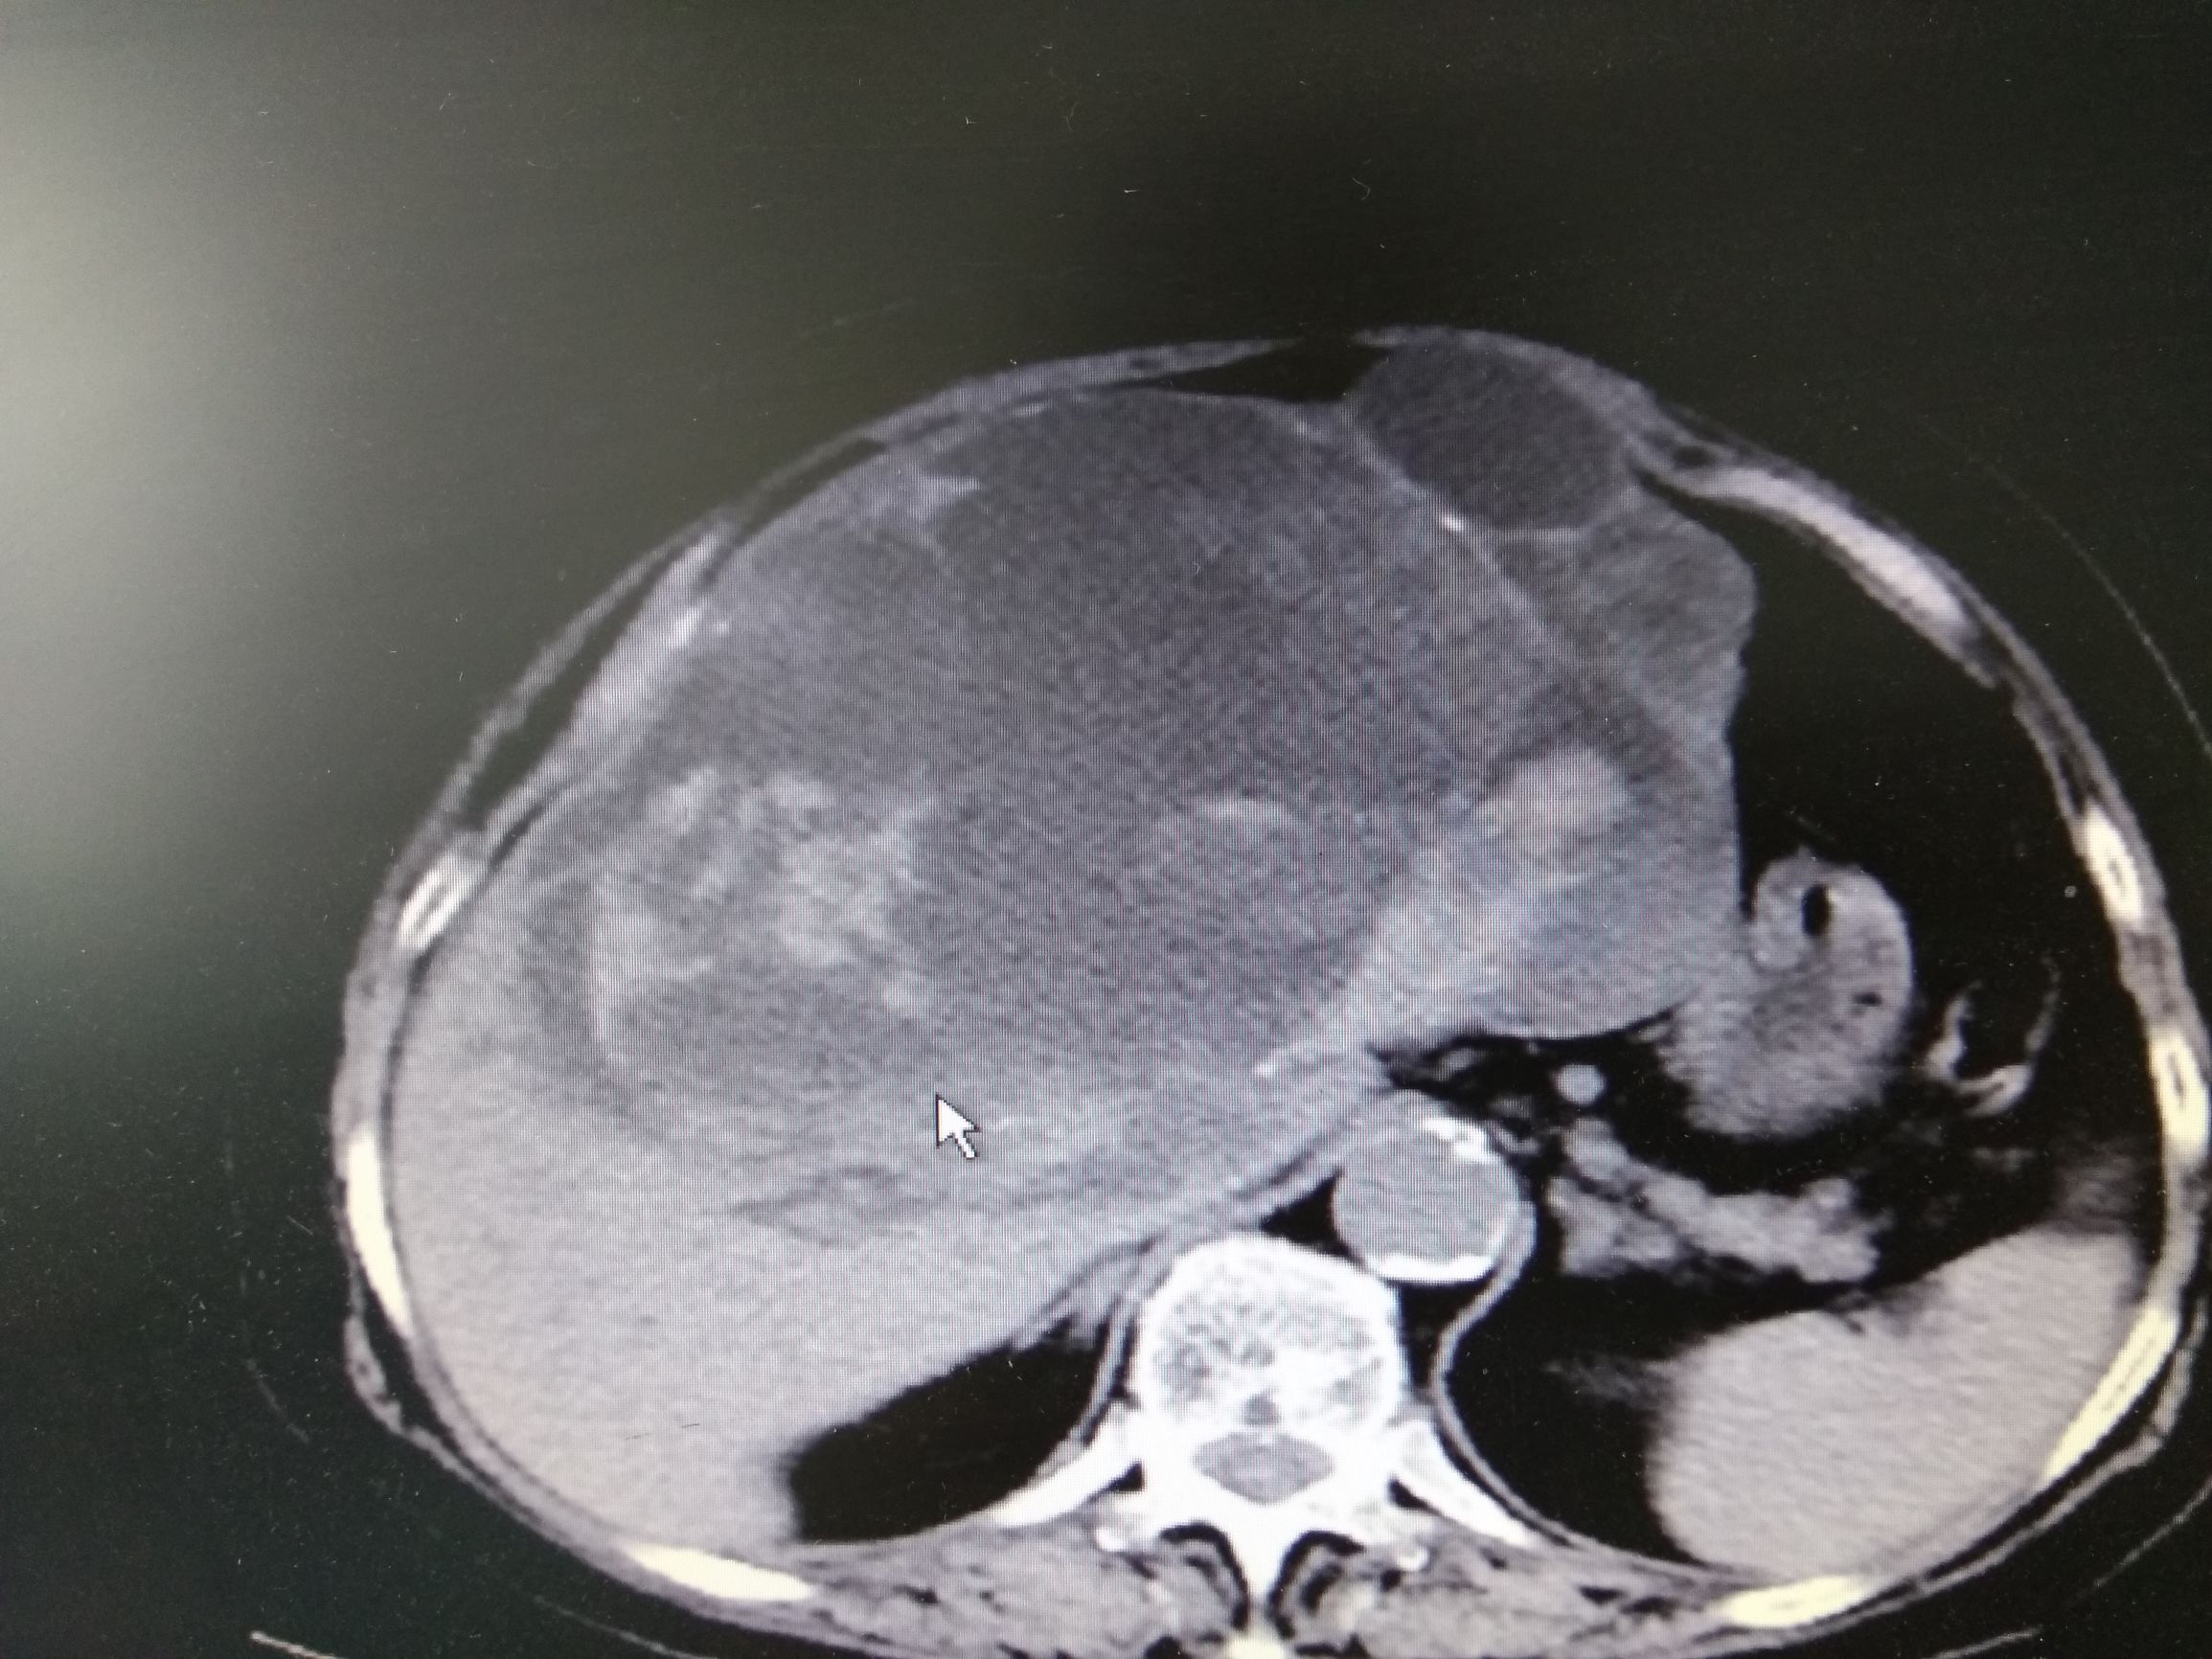

可是过了不到一个月李奶奶再次出现了腹胀,并且伴有发热,李奶奶再次来到了医院,医生复查CT,CT结果囊肿又变大了,而且囊肿里面有高密度,医生解释那有可能是出血,于是李奶奶再次做了穿刺抽液,抽出来的是血性混浊的液体,但是过了几天再次复查积液又多了,而且发热症状不缓解,这时候医生开始怀疑病人的疾病可能不是简单的肝囊肿,做了肝脏强化CT检查,并且检查了肿瘤标记物,CA199,CEA升高,在查阅很多文献,以及请相关专家会诊以后考虑李奶奶这个病就是肝脏囊腺癌,是一种比较少见的肝脏癌症。